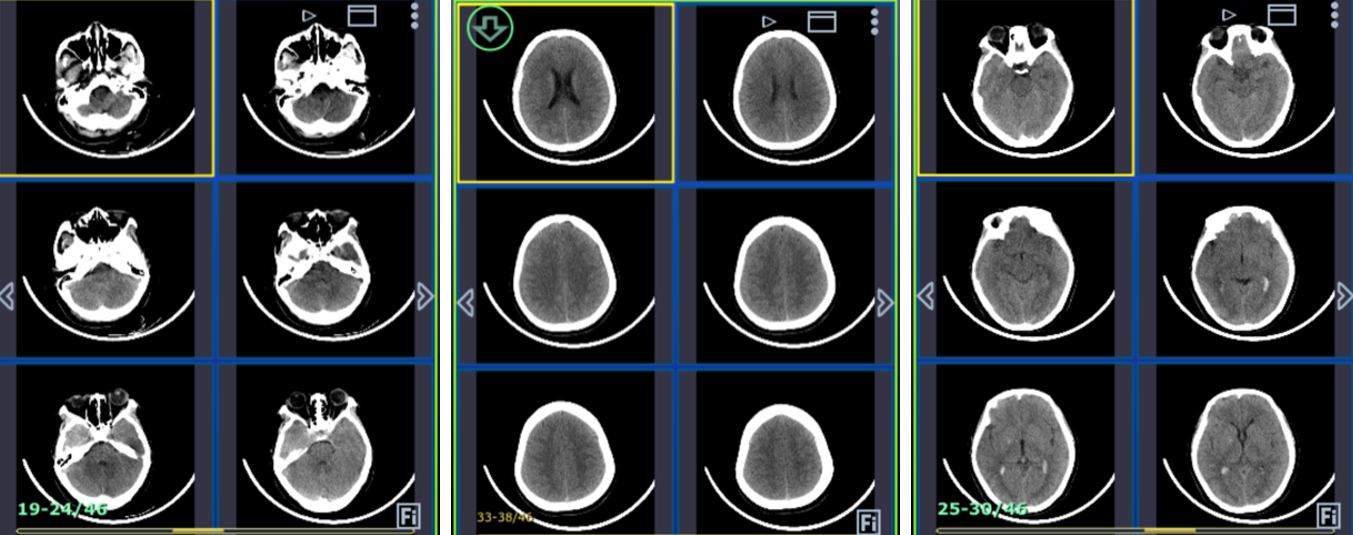

主诉:1月前突发剧烈头痛发作。

查体:GCS 15,四肢肌力正常。

认知功能:MMSE:24;MOCA:25。

烟雾病

脉络膜前动脉假性动脉瘤

术后CT